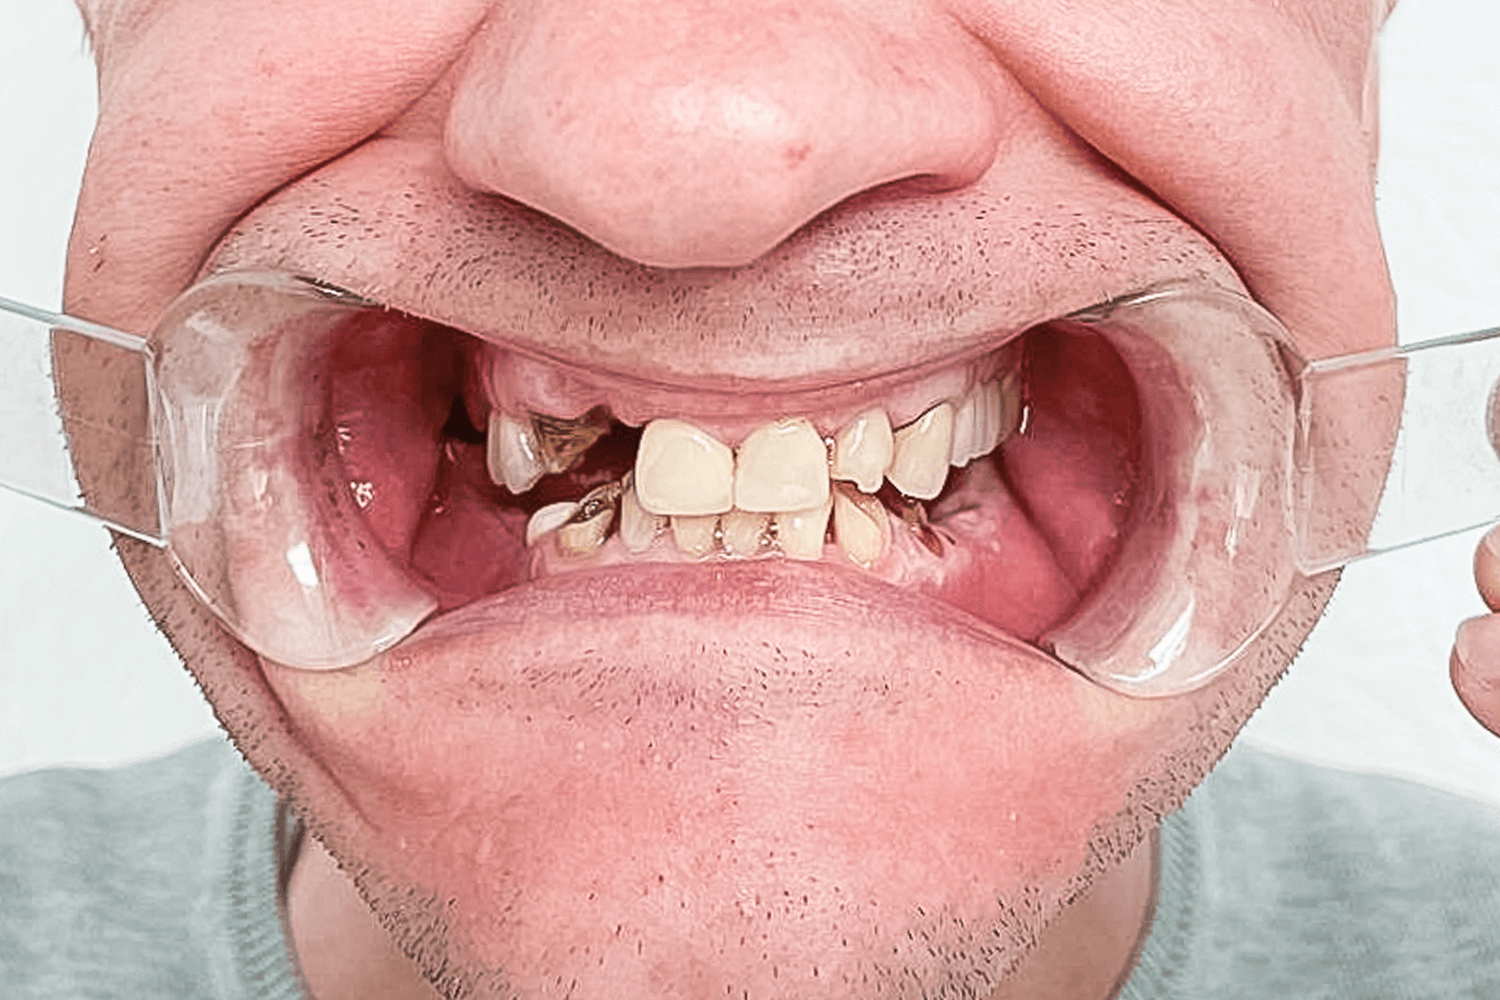

При осмотре пациента было обнаружено отсутствие восьми зубов: 5, 6, 7, 8 с правой и левой сторон на нижней челюсти. Нижние фронтальные зубы были поражены в результате патологического стирания вызванного массивной антагонистической конструкцией (металлокерамические коронки) на фронтальных зубах верхней челюсти. После 3D КТ-диагностики, осмотра и выслушав пожелания пациента, предложили следующий план лечения:

На первичной консультации врач провел осмотр полости рта, оценил КТ-снимки, составил план лечения и согласовал его с пациентом.